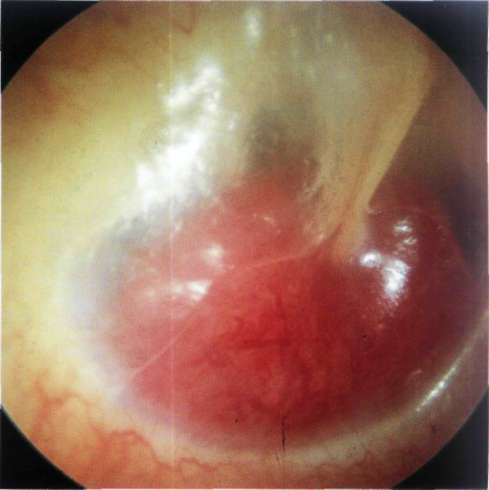

Obstrucción de la exóstosis del auditivo externo canal que resulta en otitis externa debido a la acumulación de células escamosas dentro del canal. La cirugía es esencial tanto para evitar la formación de colesteatoma y mejorar la audición